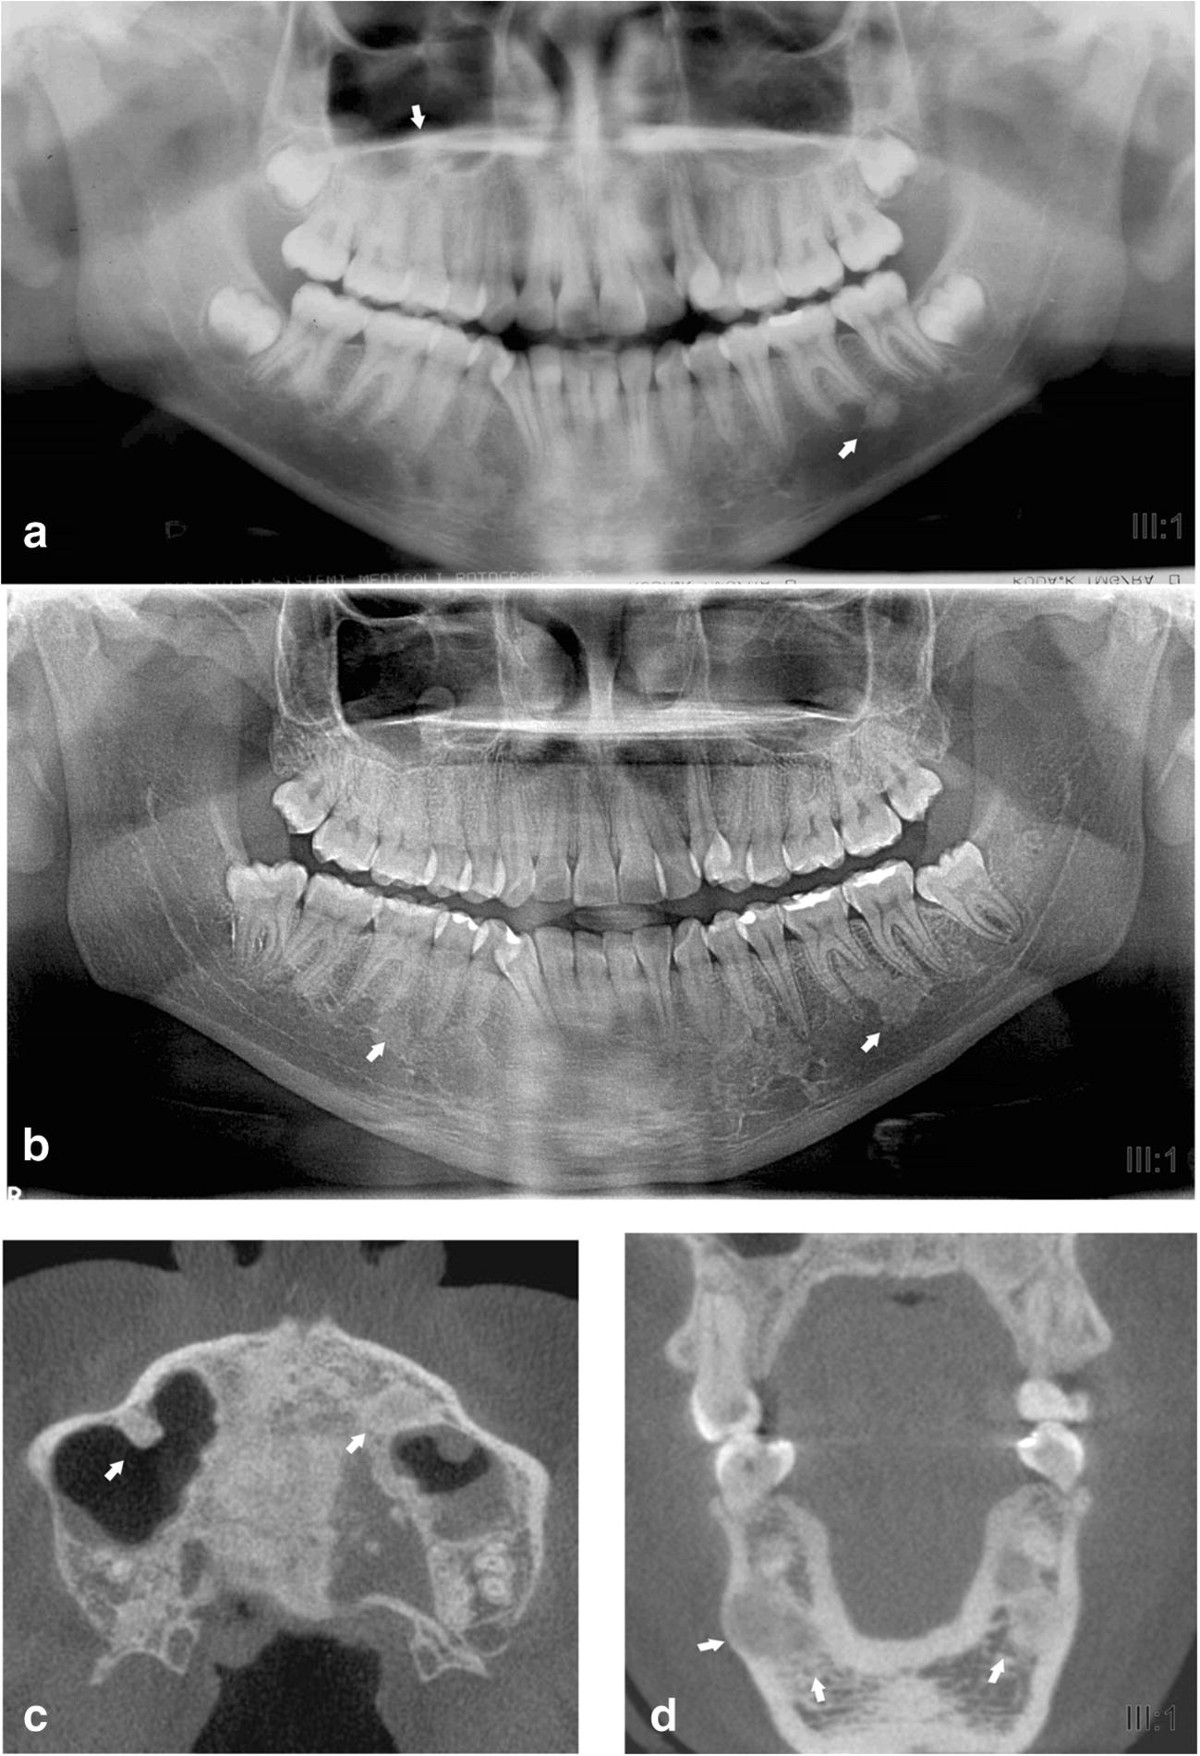

A case report of Gardner syndrome with hereditary widespread osteomatous jaw lesions - Oral Surgery, Oral Medicine, Oral Pathology, Oral Radiology and Endodontics

image size: 2210x1124